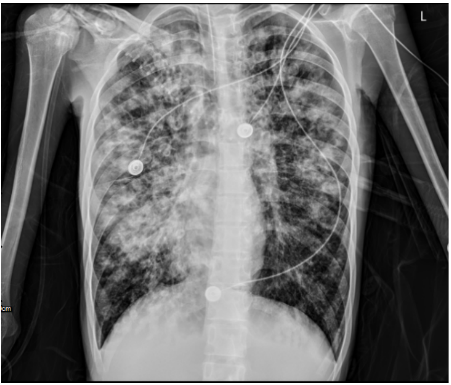

床旁胸:两肺弥漫渗出、局部实变,右肺为著(图1)

1  2023年8月15日床边胸部X线

8月28日复查胸部X线片两肺弥漫渗出、局部实变,右肺为著(图8)

图8  床旁胸部X线片(左为8月28日,右为8月11日)